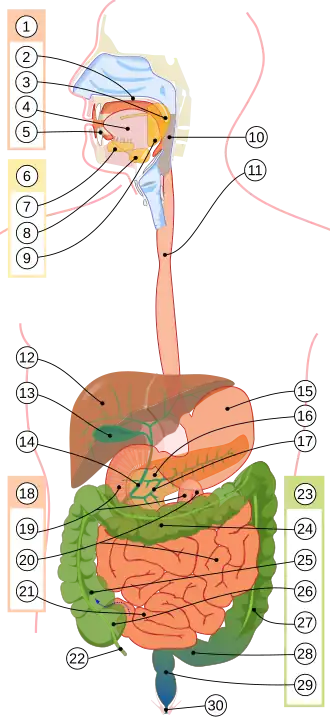

Гастроэнтерология

- 1

- Ротовая полость

- 6

- Слюнные железы

- 11

- Пищевод

- 12

- Печень

- 13

- Желчный пузырь

- 14

- Общий желчный проток

- 15

- Желудок

- 16

- Поджелудочная железа

- 17

- Проток поджелудочной железы

- 18

- Тонкая кишка

- 22

- Аппендикс

- 23

- Ободочная кишка

- 24

- Поперечная ободочная кишка

- 25

- Восходящая ободочная кишка

- 26

- Слепая кишка

- 27

- Нисходящая ободочная кишка

- 28

- Сигмовидная кишка

- 29

- Прямая кишка

- 30

- Анус

Гастроэнтероло́гия (от др.-греч. γαστήρ, γαστρός — желудок + др.-греч. ἔντερον — кишка, кишки, кишечник + др.-греч. λόγος — учение) — раздел медицины, изучающий желудочно-кишечный тракт (ЖКТ) человека, его строение и функционирование, его заболевания и методы их лечения.